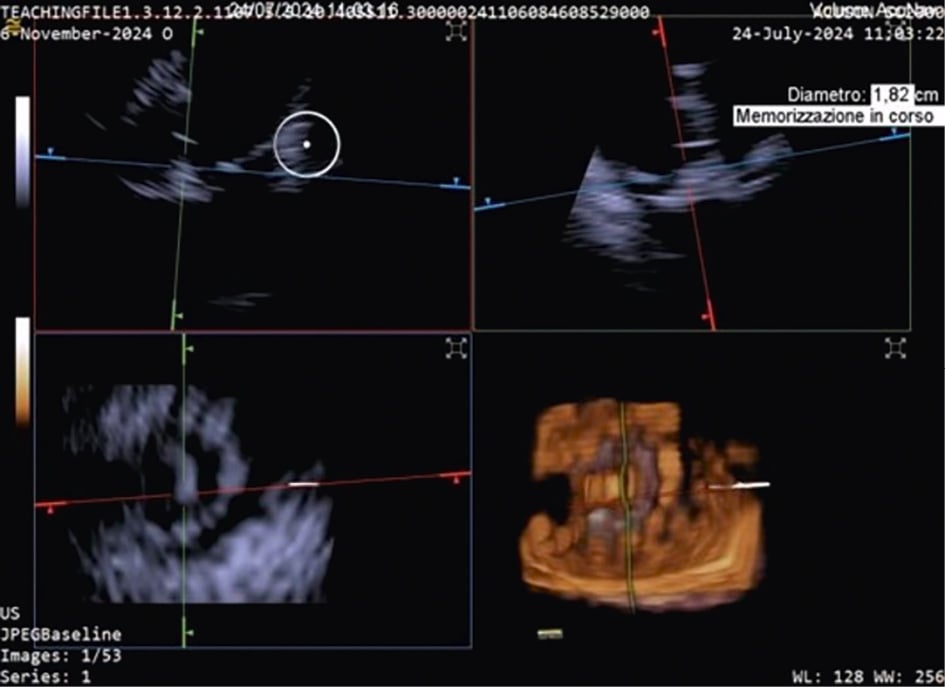

TTVR is a new technology used for tricuspid regurgitation (TR) treatment in patients not eligible for other percutaneous approaches23. The suitability for this treatment mainly depends on the annular dimensions, and unlike other treatment approaches, the imaging quality requirements are not very strict24. Three-dimensional ICE plays a crucial role in guiding the TTVR procedure, especially when TOE imaging is technically challenging. There are currently some cases described in the literature in which TTVR procedures are performed using combined 3D TOE-ICE imaging. Furthermore, there are only a limited number of centres with experience in ICE-guided TTVR24, but considering the advantages of image quality, it could become the standard in the coming years. Typically, the ICE probe is inserted via transfemoral or transjugular access and positioned in the middle of the RA. By placing the 3D ICE probe directly in the RA, the problem of acoustic interference can be overcome. Furthermore, this position allows for stable visualisation of the TV and enables the acquisition of a 3D MPR by placing the region of interest over the TV annulus, creating a 3D en face view. The leaflet capture and the valve implantation can be guided stepwise with 3D MPR25. A dedicated echocardiographer is essential to create and optimise the imaging modalities (TOE and ICE). In fact, considering that intraprocedural echocardiographic guidance is essential for procedural success, the interventional imager plays a crucial role in guiding the implantation of the device. Figure 5, Figure 6 and Moving image 8 show a Cardiovalve case (Venus Medtech) and a LuX-Valve case (Jenscare Scientific).

Figure 5. 3D MPR ICE imaging showing Cardiovalve device opening at the level of the tricuspid annulus. 3D: three-dimensional; ICE: intracardiac echocardiography; MPR: multiplanar reconstruction

Figure 6. Three-dimensional MPR views of the tricuspid valve after LuX-Valve deployment. The atrial en face view allows the evaluation of possible residual leakage. MPR: multiplanar reconstruction

Moving image 8. 3D MPR views and 3D MPR colour of the TV after LuX-Valve deployment. The atrial en face view (bottom left) allows evaluation possible residual leakage.